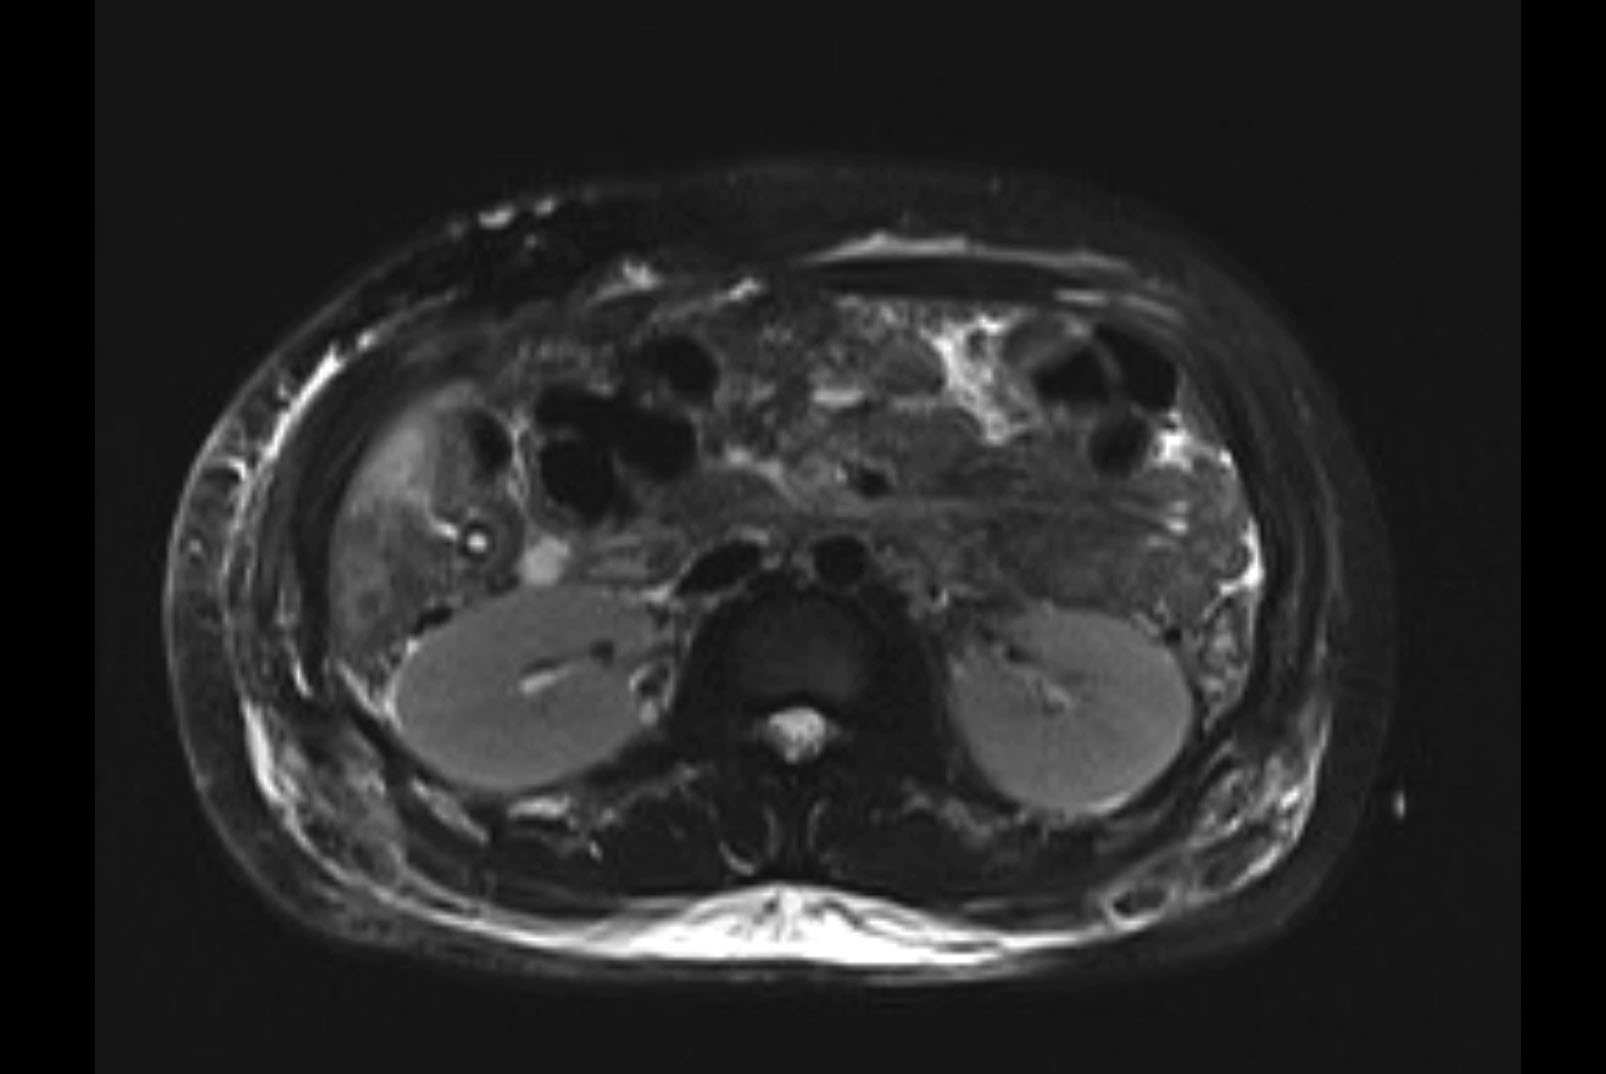

Imaging Analysis

Look through the patient's CT scan to identify any areas of concern for the necessary procedure.

MRI T2

Based on initial findings, which issue(s) would you be most concerned about?